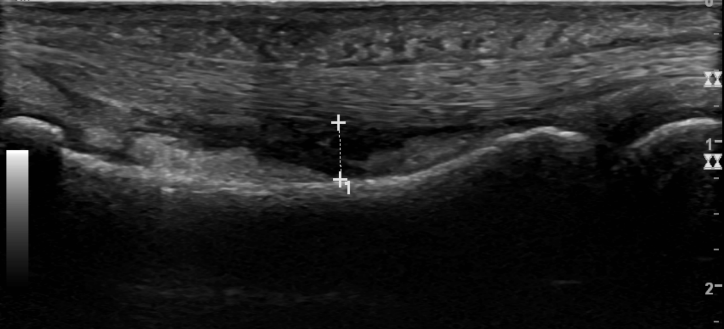

3. A2 annular pulley injury with bowstring deformity of flexor tendon